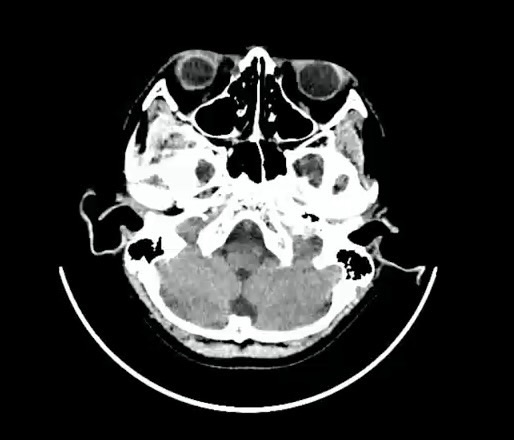

【患者信息】:男,10岁。

【主诉】:头部外伤。

脑外伤 (39)